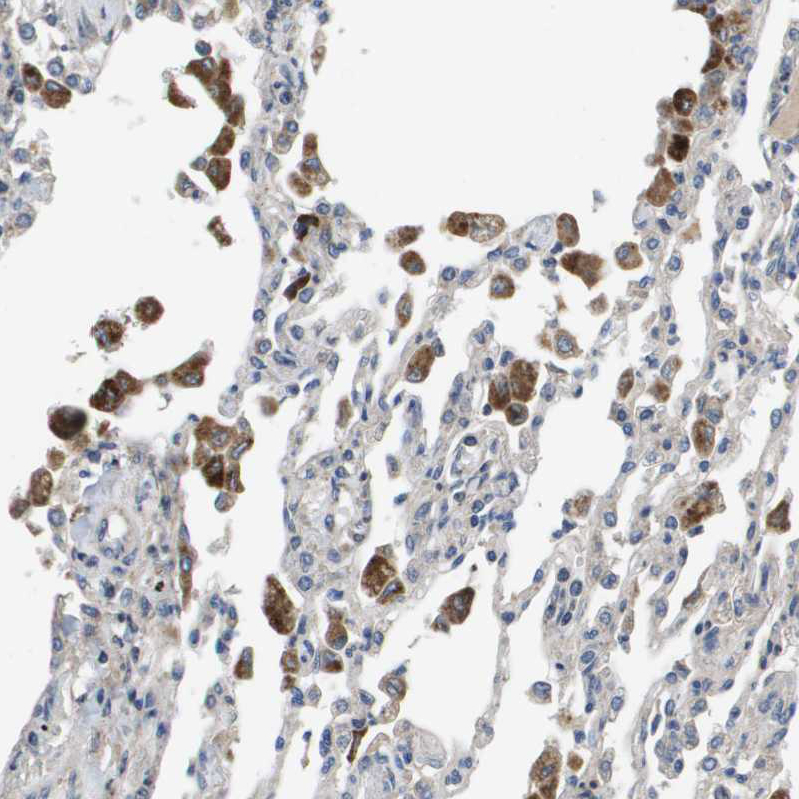

Immunohistochemical staining of human lung shows moderate cytoplasmic positivity in macrophages.